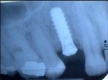

Ein Implantat ist ein künstlicher Zahnersatz. Es ist zumeist ein zylinderförmiger Metallstift aus Titan oder Keramik, der in den Kieferknochen eingesetzt wird. Dabei entsteht nach einer gewissen Einheilungsphase eine starre Implantat - Knochenverbindung. Titan ist ein äußerst gewebeverträgliches Material (biokompatibel, keine allergischen Reaktionen bekannt) und wird z.B. auch in der Orthopädie (z.B. künstliche Hüfte) erfolgreich eingesetzt.

Das Implantat kann dabei jeden Zahn einzeln ersetzen oder auch als Verankerung für Brücken oder Prothesen dienen. Ein wesentlicher Vorteil liegt darin, daß keine gesunden Nachbarzähne abgeschliffen werden müssen und der Knochenschwund (Resorption) verlangsamt werden kann. Implantate leiten die Kaukräfte wie Zähne in den Knochen, dadurch erhalten sie den Kieferknochen und das Zahnfleisch.